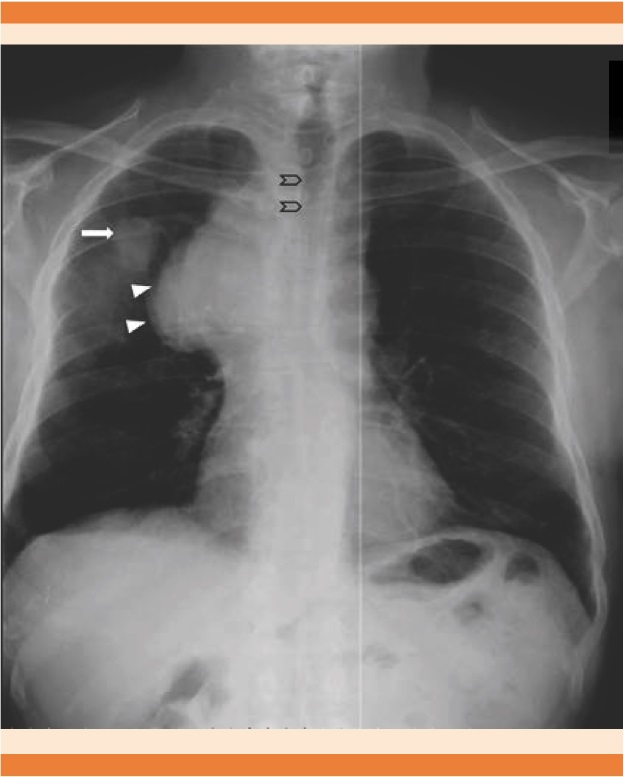

La radiografía de tórax (Figura 6) es el estudio de imagen inicial y es primordial para decidir el siguiente paso.14 La inyección de medio de contraste para observar la vena cava (cavografía) es el patrón de referencia para confirmar el grado y nivel de la obstrucción.4 A partir de los estudios de tomografía con medio de contraste, la cavografía prácticamente no se realiza en la actualidad; sin embargo, es indiscutible su utilidad práctica para valorar la colocación de endoprótesis.15

Figura 6 Radiografía simple de tórax de un paciente masculino de 81 años de edad con diagnóstico de cáncer pulmonar de células pequeñas en la que se observa ensanchamiento del mediastino (cabezas de flecha), compresión de la vía aérea (chevrones) y nódulo pulmonar metastásico derecho (flecha).